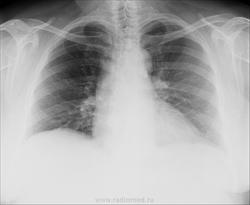

Женщина, 64года, пришла на прием с жалобами на длительный кашель. Снимки не очень качественные и без описания. Помогите разобраться. Признаки застоя? Интенсивная очаговая тень слева это что?

имхо: слева параортально петрификт.Признаков застойных изменений не вижу.

См. рис. Обызвествленный ЛУ. Поддерживаю коллег.

ИМХО. Петрификат - обызвествленный лимфатический узел, а очаг Гона - обызвествленный   участок первичного поражения легочной ткани.

Участок дистрофии или некроза ткани, инкрустированный солями кальция можно называть петрификатом(petrificatum; греч. petros камень + лат. facio делать) , кальцинатом, обызвествленным очагом (фокусом). Очаг Гона - обызвествленный, петрифицированный, кальцинированный первичный аффект в лёгком.